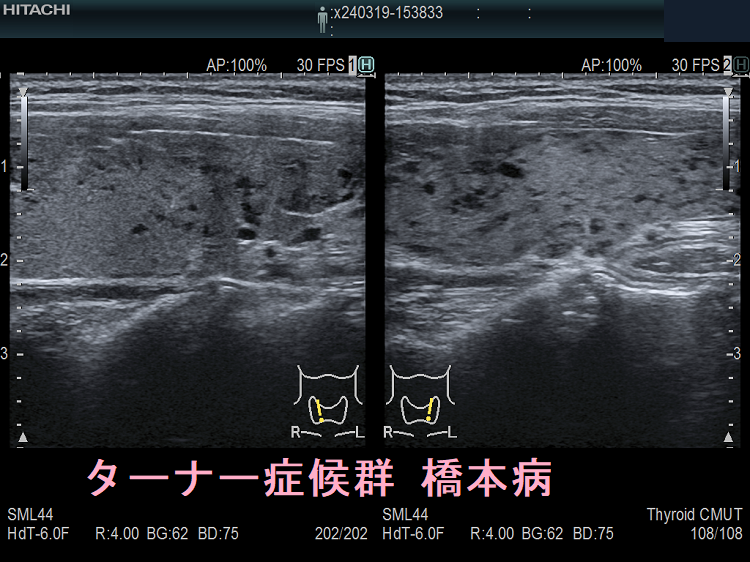

ターナー症候群と橋本病(TURNER SYNDROME FOUNDATION HPより改変)

ターナー症候群では甲状腺の病気(甲状腺機能亢進症、甲状腺機能低下症/橋本病)の合併率が高い(43.8%)とされます。(J Pediatr Endocrinol Metab. 2015 Jan;28(1-2):201-5.)(J Endocrinol Invest. 2011 Apr;34(4):260-4.)

6~18歳のターナー症候群女子において、26.8%で抗甲状腺ペルオキシダーゼ抗体(TPO抗体)、抗サイログロブリン抗体(Tg抗体)のいずれか、あるいは両方が陽性。(Adv Exp Med Biol. 2017;1022:71-76.)